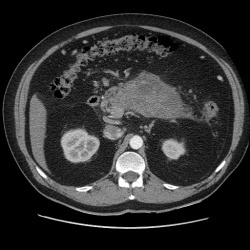

Женщину направили с УЗИ с подозрением на образование надпочечника. Образование действительно тесно приелегает к медиальной ножке надпочечника, но честно говоря первый раз такое вижу, состоящее из 2х...